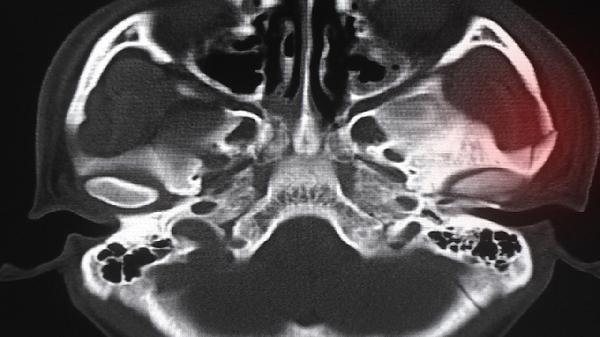

对宽大鼻骨进行截骨后向中线推移,从根本上改善鼻头宽大问题。适合先天性鼻骨过宽者,需全麻下操作并佩戴鼻托4-6周。存在骨痂增生风险,需定期复查骨愈合情况。